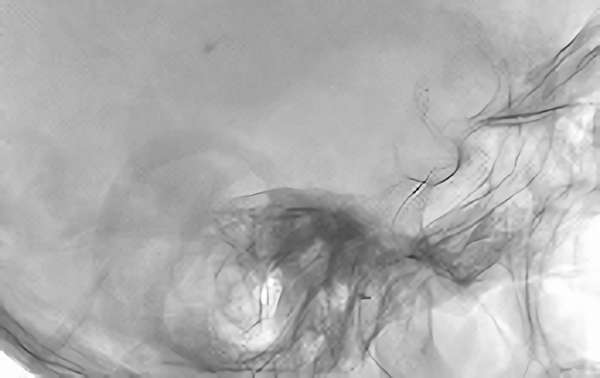

症例 '20年7月

No.

839

'20年7月2日

心原性脳梗塞症

90代

院内外来

手術写真

治療

前

中

後

手術日